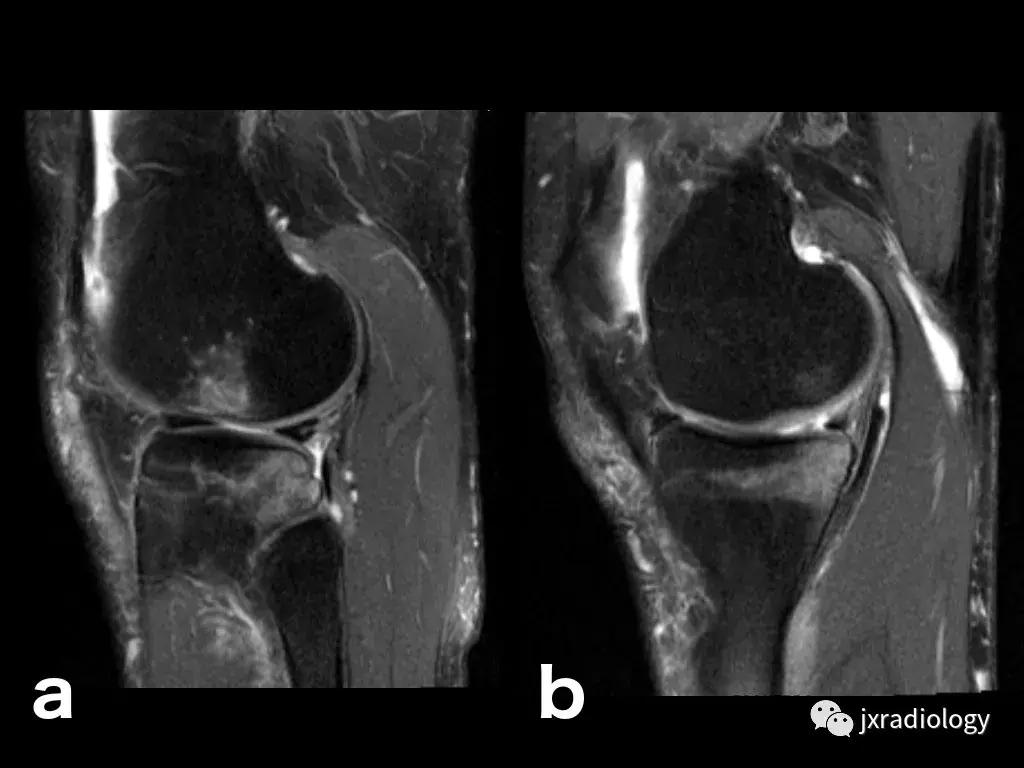

图25:短暂性骨髓水肿综合征(短暂性骨质疏松症):30岁女性急性膝部疼痛的矢状位FS-PDWI MR影像显示骨髓水肿,涉及非负重区域股骨外侧髁骨髓水肿在1年内几乎完全自发消退。短暂性骨髓水肿综合征是自限性病变,其表现为与MRI研究中的骨髓水肿证据相关的关节痛。其病因仍不确定。

图26:局限性游走性骨质疏松症(具有位置变化的短暂性骨髓水肿综合征)(连续冠状PD-FS-WI):在一些情况下,在连续MRI上看到骨髓水肿的位置变化,这被称为局限性游走性骨质疏松症(RMO);尽管可以自愈的短暂性骨髓水肿综合征的情况更为常见,但可以在一小部分病例中转移到不同的关节,或者(甚至更罕见)转移到同一关节内的不同部位(关节内转移) ,如关于该患者所见。在这个关节内RMO病例中,没有创伤史,水肿始于股骨内侧髁,3个月后发现转移到外侧髁。